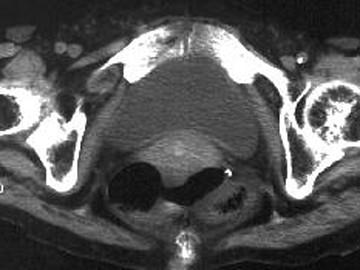

问题 女,69岁,阵发性腹痛伴恶心呕吐7h,10年前因右侧腹股沟斜疝行手术治疗,因急性肠梗阻行CT扫描如图,最可能的诊断是 ( )

选项 A、半月线疝 B、闭孔疝 C、股疝 D、腹外斜疝 E、急性肠梗阻

答案 B